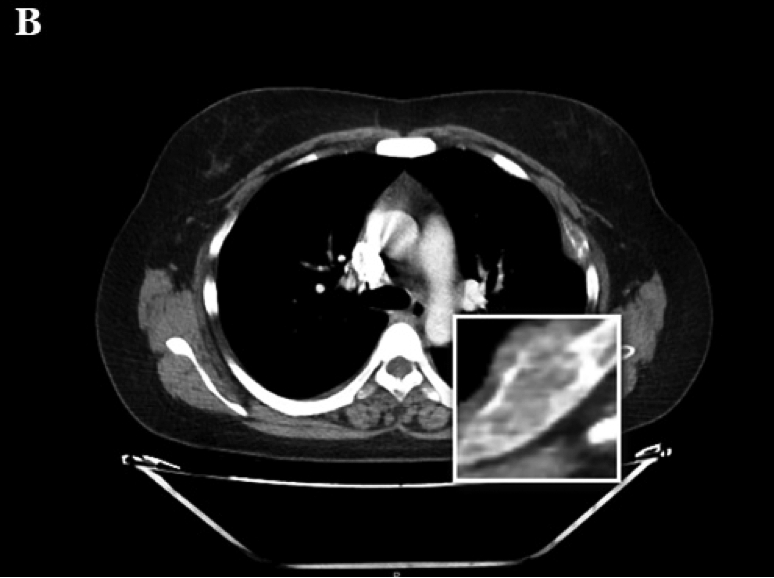

Ante la sospecha clínica de tumores pardos múltiples versus enfermedad metastásica se realiza IC con Oncología y en conjunto se solicitaron los siguientes estudios, que informaron como positivo: a) TAC de tórax, abdomen y pelvis (con contraste): leve enfisema centrolobulillar bilateral, opacidades nodulares con densidad de partes blandas (LSD y LSI). Resto de los órganos normales, no adenomegalias. Presencia de múltiples lesiones osteolíticas a nivel de todos los cuerpos vertebrales, esternón, región anterior de varias costillas, húmero, sacro, y porción visible de ambos ilíacos (Figuras 2, 3 . 4 A); b) TAC de cuello (con contraste): múltiples lesiones osteolíticas en la columna cervical.